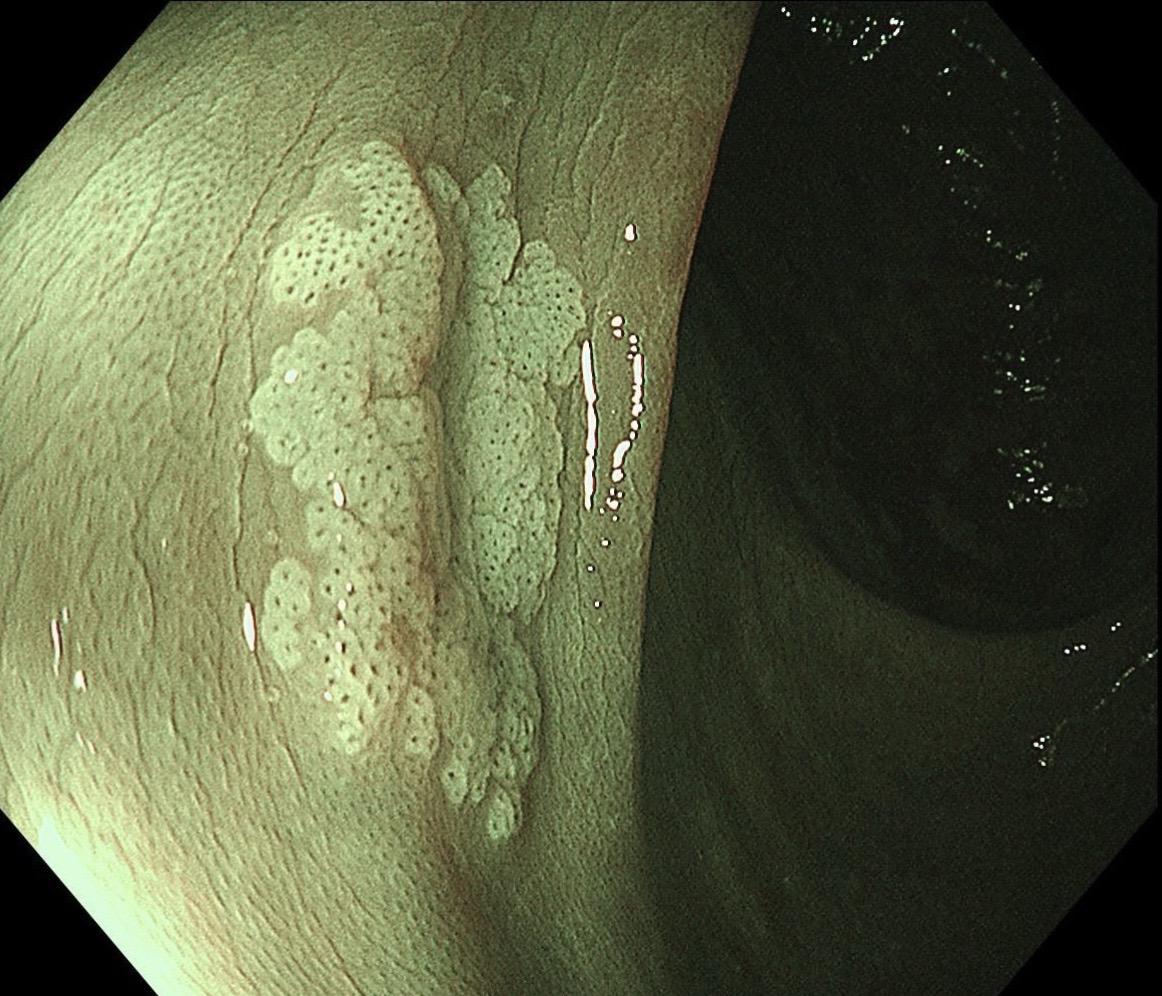

结肠SSL 醋酸染色。染色效果不亚于靛胭脂,结合NBI,Near focus观察表面结构非常OK,下次让护士长买大桶装的,1桶6块9,可以喷一年,哈哈……

结肠SSL 醋酸染色。染色效果不亚于靛胭脂,结合NBI,Near fo...